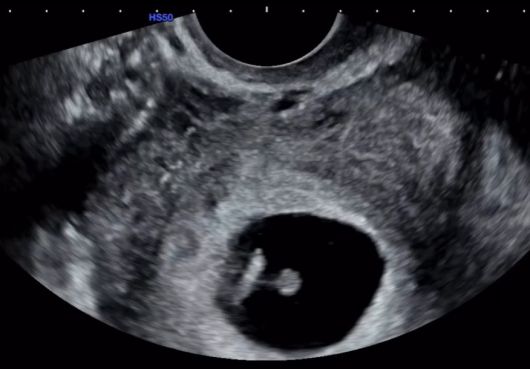

그러면서 "지금 이 순간을 떠올리면, 그 모든 시간들이 이 기적 같은 오늘을 위한 준비였던 것 같다"며 "정말 감사하게도 저를 있는 그대로 온전히 사랑해 주는 사람을 만나게 되었고 그 사랑이 단 한 번에 기적이 됐다"라며 임신 소식을 전했다.

연애 및 결혼 발표를 하기 전 혼전임신 발표를 하게 된 16기 옥순에 대해 관심이 쏠리고 있다. 16기 옥순은 앞으로 SNS를 통해 임신과 육아에 대해 이야기하겠다고 밝혔다.